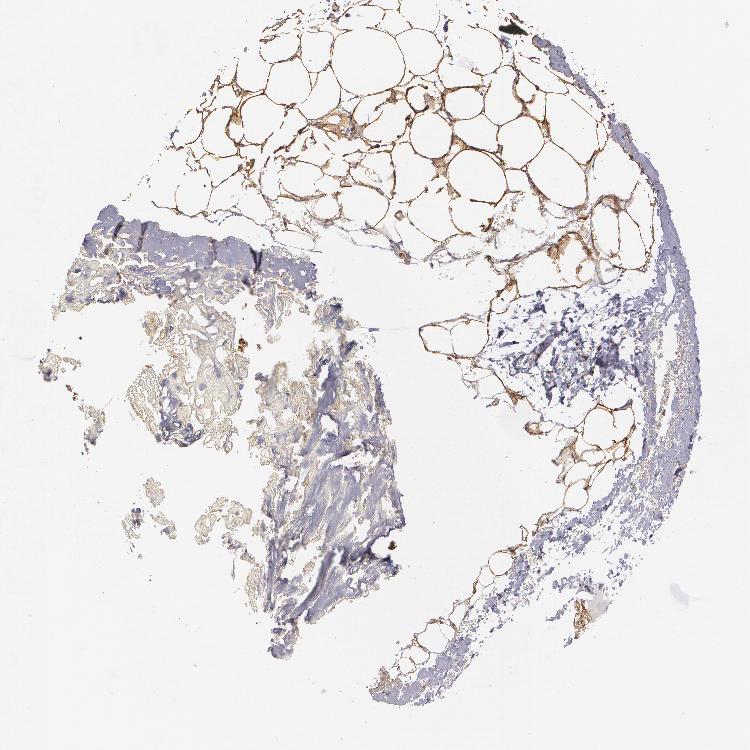

BREAST - Antibody stainingi

Antibody staining in the annotated cell types in the current human tissue is reported as not detected, low, medium, or high, based on conventional immunohistochemistry profiling in selected tissues. This score is based on the combination of the staining intensity and fraction of stained cells.

Each image is clickable and will lead to virtual microscopy that enables deeper exploration of all samples and also displays staining intensity scores, fraction scores and subcellular localization as well as patient and tissue information for each sample.

Antibody HPA001566

Adipocytes High